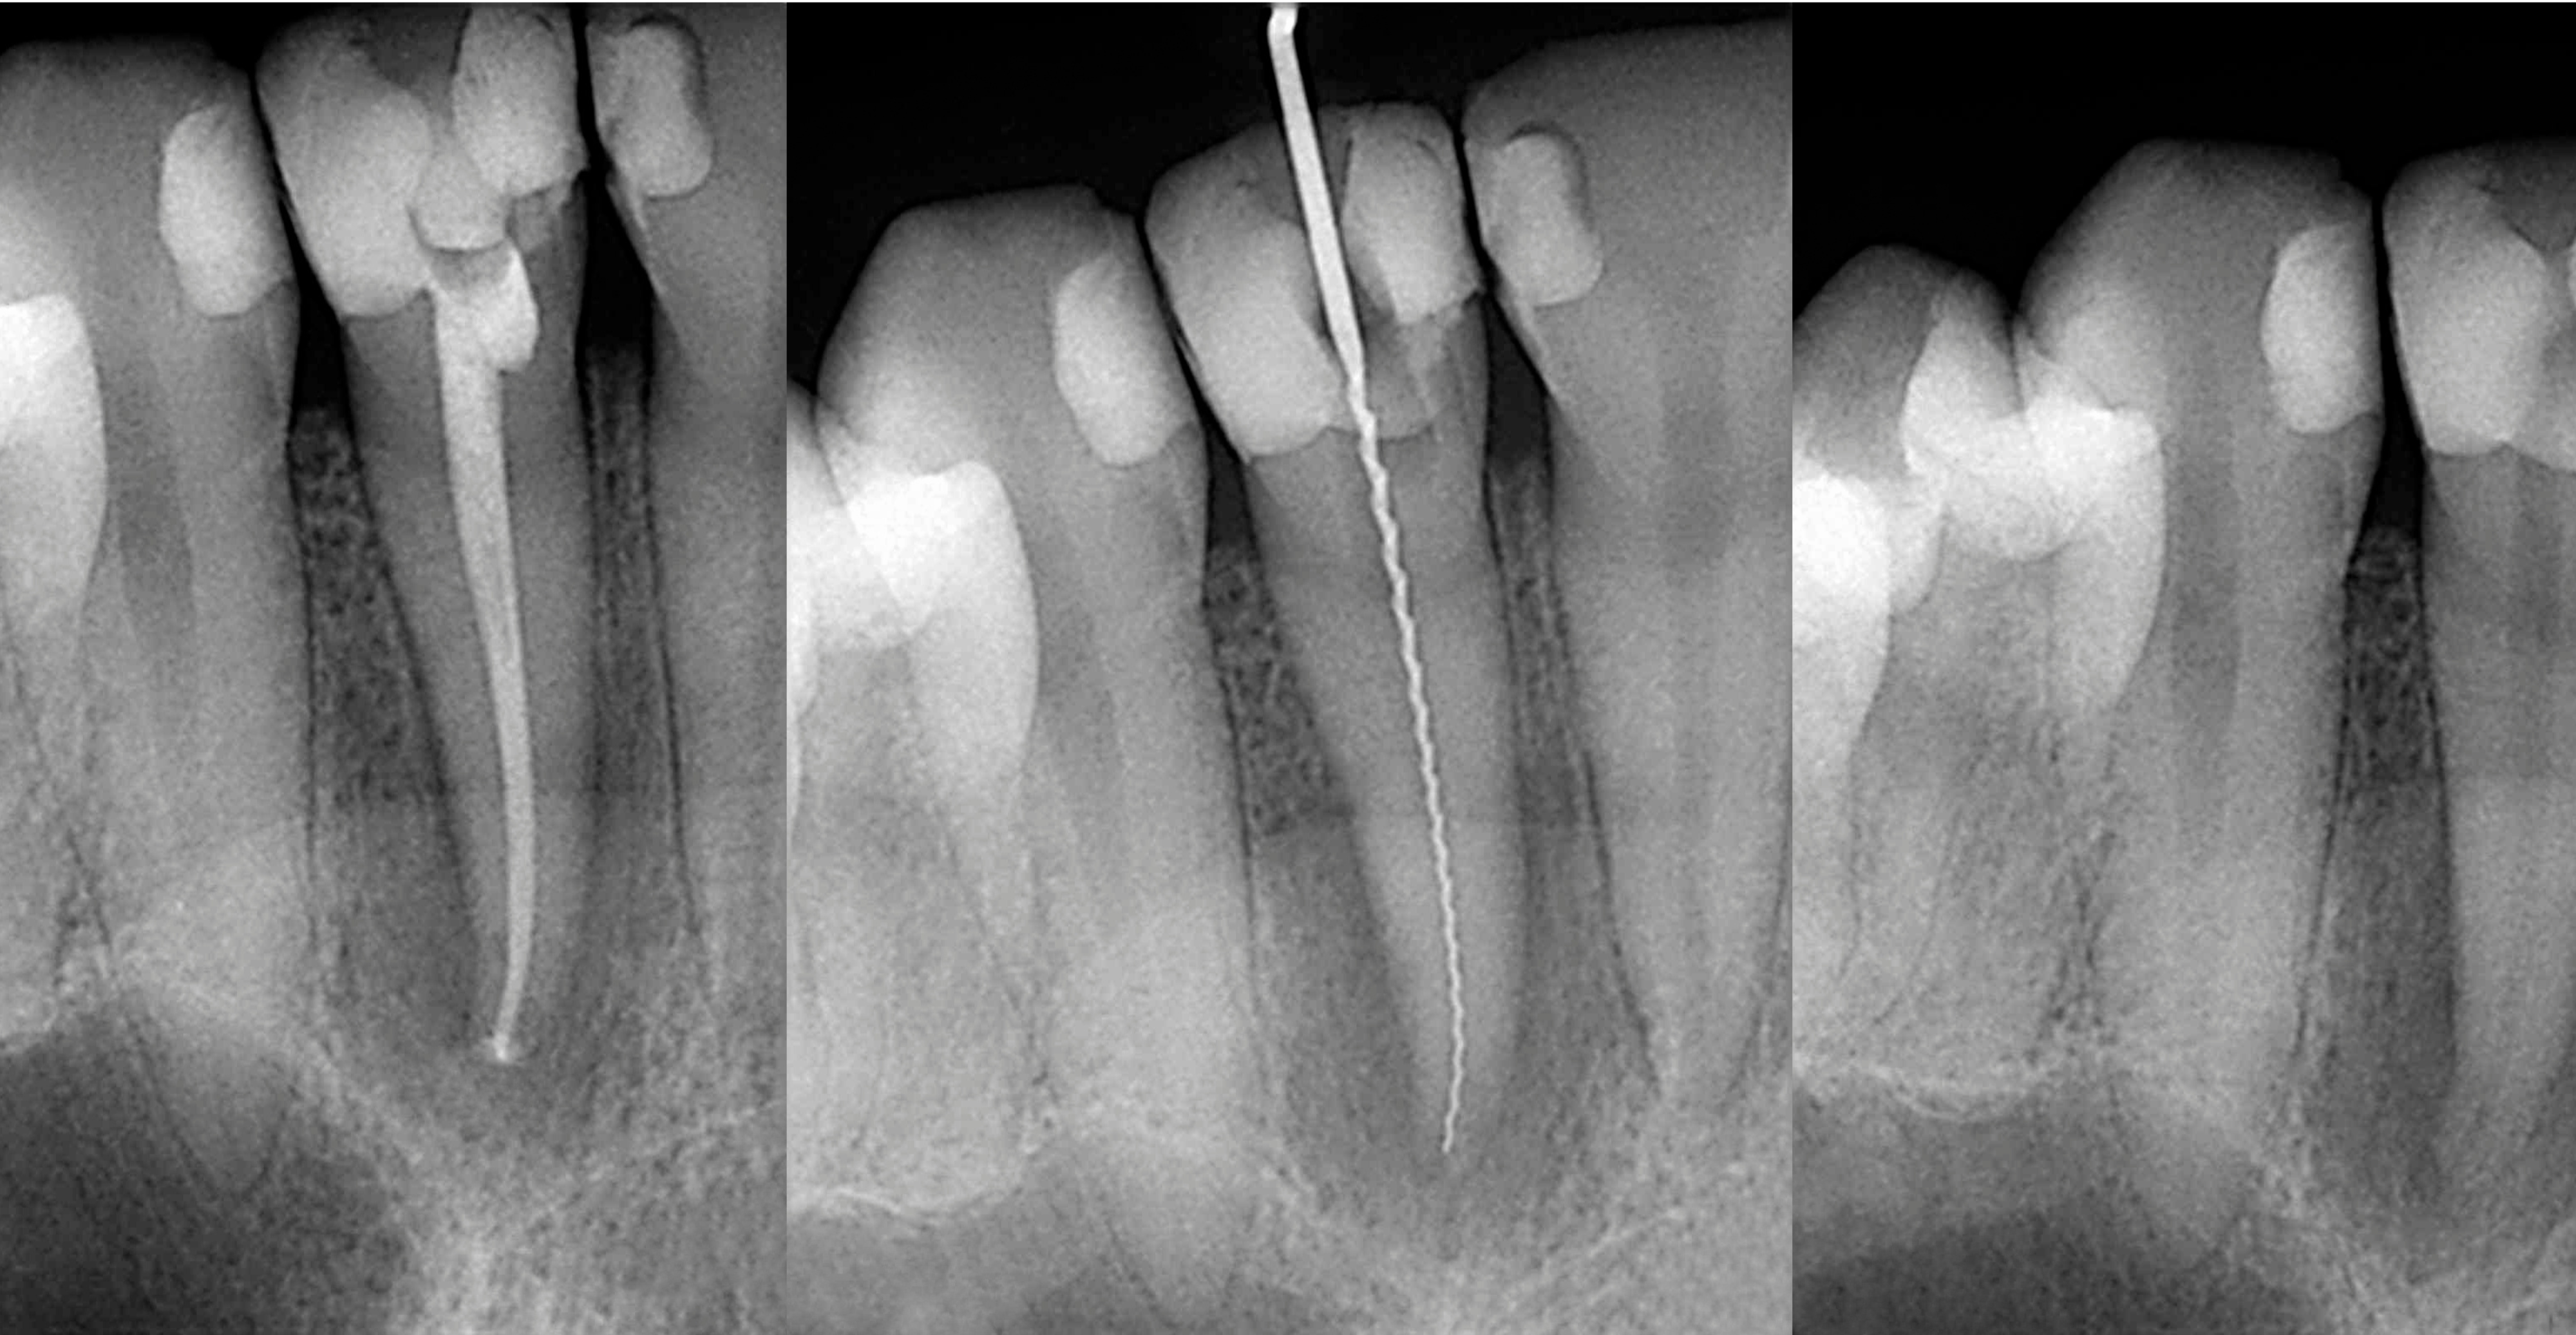

If you’re experiencing tooth pain, sensitivity to heat or cold, or swelling, you may have a deep tooth infection that requires a root canal. At Downtown Dental, we perform gentle and effective root canal therapy to remove infected tissue and save the natural tooth—preventing extraction.

The procedure involves cleaning and disinfecting the root canals, then sealing the tooth with a filling or crown. With today’s modern techniques and local anesthesia, most patients say the process is no more uncomfortable than getting a filling. Save your smile—and your peace of mind—with Downtown Dental.